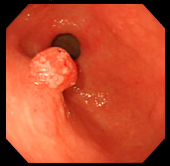

| 切除した部分をクリップで止血 | ポリープ切除した部分の1ヶ月後の粘膜 | ||